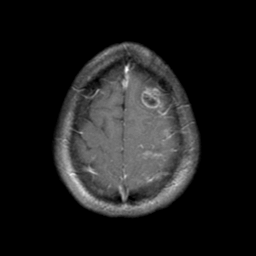

Sarcoma, MR Study #1 mr-gad -- Slice #21

[Home][Help][Clinical] Slice 21